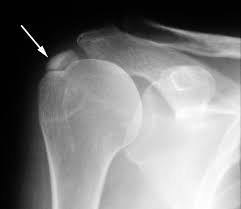

Đầu tiên, bác sĩ sẽ hỏi bạn về các triệu chứng mà bạn đang gặp phải. Tiếp theo, bác sĩ sẽ tiến hành thăm khám khớp vai của bạn để kiểm tra tầm vận động của khớp vai cũng như xác định các điểm đau của bạn. Tuy nhiên, hiện tượng đau vai và sự hạn chế chuyển động của viêm gân vôi hóa ở vai dễ bị nhầm lẫn với các cơn đau vai khác, vì vậy phương pháp chẩn đoán đầu tay là chụp phim X-quang khớp vai. Hình ảnh X-Quang sẽ cho thấy rõ sự lắng đọng canxi trong gân và xác định vị trí gân bị vôi hóa.

Khi đã xác định bạn bị viêm gân vai vôi hóa, bạn sẽ cần chụp X-quang khớp vai thêm một vài lần khác theo chỉ định của bác sĩ. Dựa trên sự thay đổi lượng canxi tích tụ, bác sĩ có thể xác định xem tình trạng bệnh của bạn sẽ tự lành hay cần phải phẫu thuật. Nếu những tổn thương vôi hóa nhỏ mới xuất hiện, hạn chế đánh giá trên phim Xquang, người bệnh có thể sẽ cần kết hợp thêm chụp cắt lớp vi tính hoặc MRI khớp vai để đánh giá thêm. Tuy nhiên, chụp Xquang khớp vai vẫn là phương pháp chẩn đoán hình ảnh đầu tay, có giá thành rẻ, dễ sử dụng.

Tóm lại, nếu nghi ngờ bệnh nhân bị viêm gân vôi hóa ở vai, bác sĩ có thể chỉ định người bệnh thực hiện phương pháp chụp X-quang để chẩn đoán phân biệt, từ đó xác định giai đoạn bệnh để đưa ra phác đồ điều trị hiệu quả.